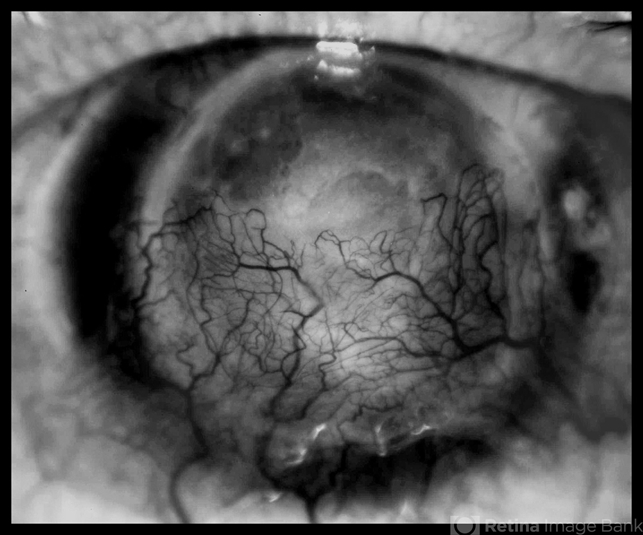

- central opacity of cornea, neovascularization (NV), corneal edema, 20 degrees

- JEFFERSON R SOUSA - Study Center and Ophthalmological Research Dr. Andre M V Gomes, Institute Dr. Suel Abujamra São Paulo-Brazil

Topcon TRC-50 DX, Imaginet 5.0, angle de 20 graus. Flash 36. - Description

- 64-year-old, patient with vision loss more than 10 years after having suffered blunt trauma with ocular perforation.